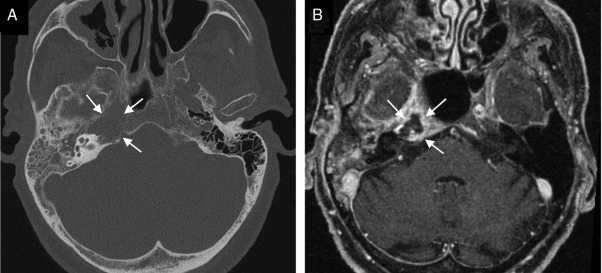

¿Cuáles son las pistas diagnósticas en la TC de la otitis media?

¿Para qué se utiliza la RM en otitis media y cuáles son sus hallazgos?

¿Cuáles son los hallazgos radiológicos en la TC de mastoiditis?

¿Cuál es una pista característica del colesteatoma?

Destruye hueso

En la RM del colesteatoma, ¿cómo se observa en T2?

Hiperintensa